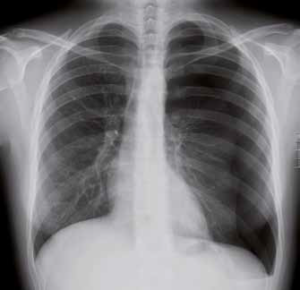

Nell’immagine in alto a destra è possibile apprezzare la radiografia di una presenza di aria tra il fegato e il diaframma come conseguenza di uno pneumoperitoneo. Nella radiografia si vede anche una banda scura di aria tra il cuore e la zona polmonare per via del passaggio di aria dal peritoneo al mediastino.

Anche nell’immagine di sinistra si vede la banda scura per via del passaggio di aria nel mediastino (frecce gialle più in basso).